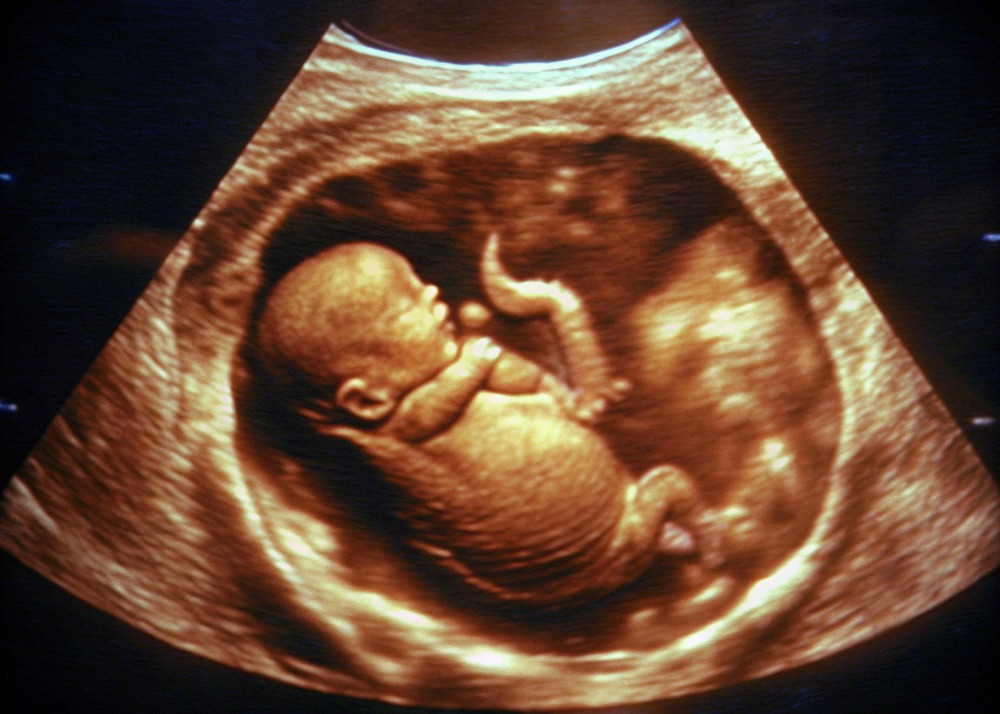

3D / 4D Pregnancy Sonography in Nashik – Seeing Growth with Reassurance

3D / 4D Pregnancy Sonography in Nashik offers more than visual clarity. It provides valuable insights into fetal development while allowing parents to feel emotionally connected to the pregnancy. Seeing detailed images often brings reassurance, especially during crucial stages of prenatal care.

At Bagul Nursing Home and Dr. Bagul’s Hope IVF Center in Nashik, advanced sonography is performed with accuracy and careful interpretation. These scans help assess growth patterns, facial features, movement, and overall well-being of the fetus. Doctors explain findings clearly, helping families understand what they are seeing rather than leaving them with unanswered questions.

For expecting parents, 3D and 4D scans also create moments of emotional bonding. Watching movement in real time often turns anxiety into calm anticipation. At the same time, the medical value remains central, allowing early identification of concerns when intervention is most effective.